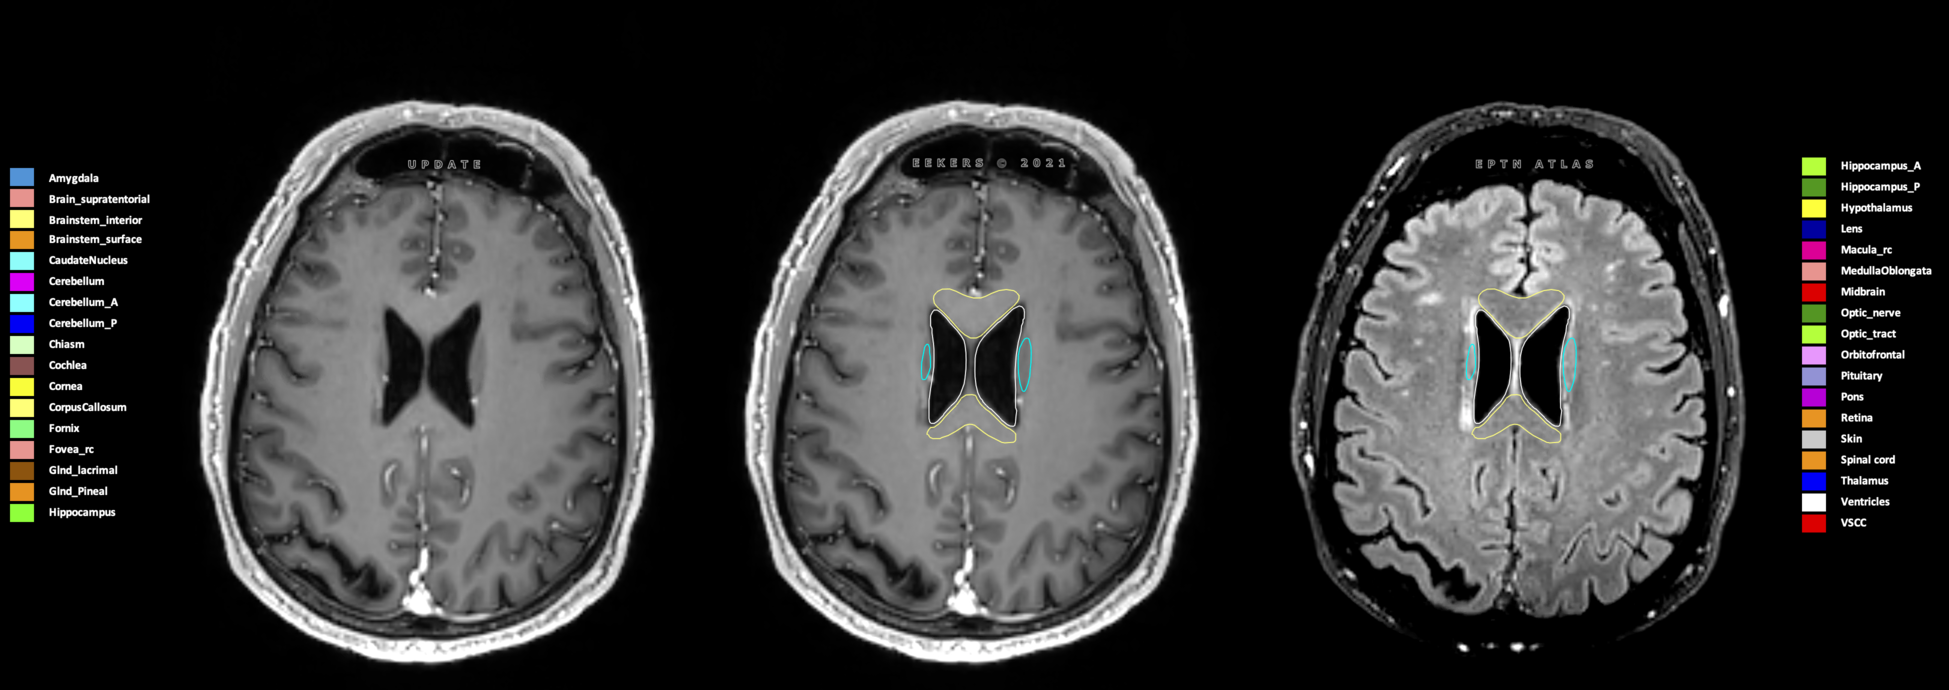

Eekers et al. have published an international neurological atlas for contouring of organs at risk in consensus with the European Particle Therapy Network (EPTN) in 2018 and an update in 2021. The purpose of this consensus atlas is to decrease inter- and intra-observer variability in delineating OARs relevant for neuro-oncology.

Included are all OARs known to be relevant for radiation-induced toxicity in neuro-oncology: brain, brainstem (midbrain, pons, medulla oblongata), chiasm, cerebellum (anterior & posterior), cochlea, cornea, hippocampus (anterior & posterior), hypothalamus, lens, lacrimal gland, optic nerve, pituitary, skin, and vestibular & semicircular canals. To further facilitate research on cognition, vision and radiological changes after irradiation of the brain, potential clinically-relevant OARs are included: amygdala, caudate nucleus, cerebellum (anterior & posterior), corpus callosum, fornix, macula, optic tract, orbitofrontal cortex, periventricular space (PVS), pineal gland, and thalamus.

Three-dimensional delineation of the 25 consensus OARs for neuro-oncology are shown on CT (WW/WL 120/40, 3000/600), 3T MR images, (T1Gd, T2FLAIR 1mm) and 7T MR (MP2RAGE 0.7 mm). All are presented in transversal, sagittal and coronal view.